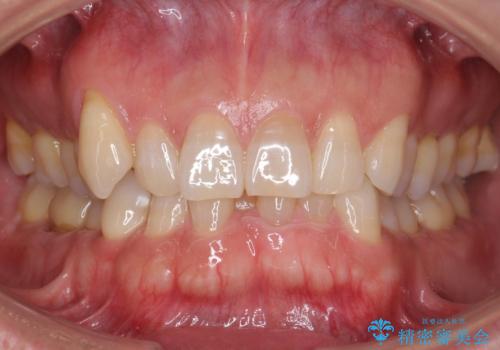

[マウスピース矯正] がたがたの歯並びをきれいにしたい

![[マウスピース矯正] がたがたの歯並びをきれいにしたいの症例 治療前](https://seimitsushinbi.jp/wp/wp-content/uploads/2025/06/0d238550c8a0fddc4de7b2c337c6c786-500x350.jpg?v=1750323380)

![[マウスピース矯正] がたがたの歯並びをきれいにしたいの症例 治療後](https://seimitsushinbi.jp/wp/wp-content/uploads/2025/06/IMG_0002-2-500x350.jpg?v=1750323305)